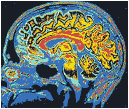

(右下图)用核磁共振拍摄的脑断面图